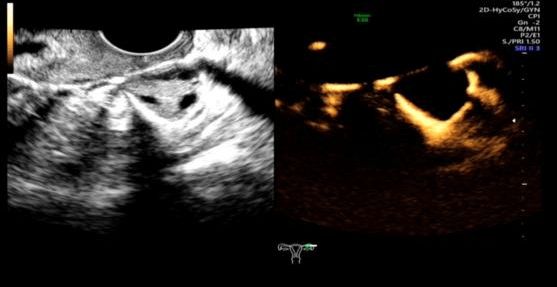

简单来说,这是一项评估输卵管通畅性的医学影像检查技术。检查时,医生会在宫腔内放置一根双腔造影管,通过推注造影剂,动态观察造影剂在宫腔、输卵管和盆腔的流动、积聚和弥散情况,从而判断输卵管的通畅度、走形以及病灶部位。通过这个快速安全的检查,输卵管的许多问题便能一目了然。

正常清晰显示双侧宫颈及输卵管

正常双侧卵巢周围造影剂呈环形包绕